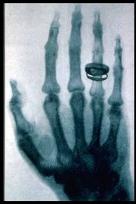

Image Acquisition Services